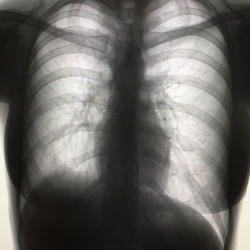

Здравствуйте, женщина 88 лет, жалобы на ухудшение самочувствия, гемоглобин 59. Лёгкие в пределах нормы?